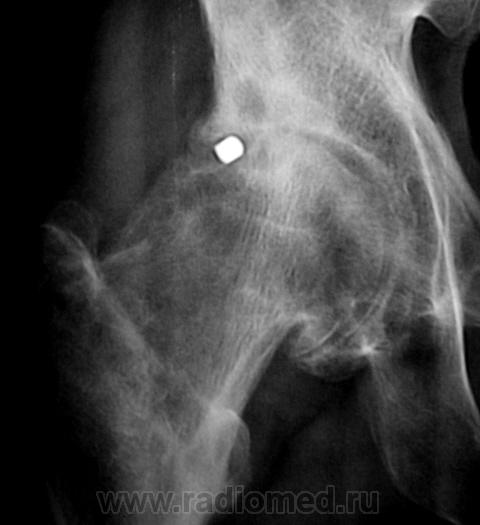

КТ 2009 года.

Продолжение.

Да, Вы правы. Пациент желает "поставить" искусственный сустав.